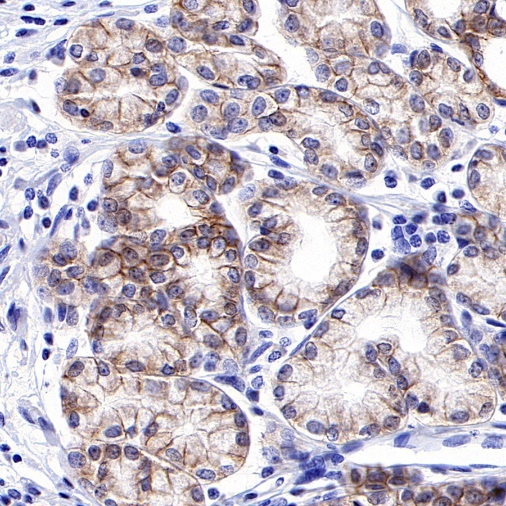

AntBio offers ROR1 recombinant rabbit monoclonal antibodies, which have been validated in human ovarian cancer, gastric cancer, endometrial cancer, and mantle cell lymphoma tissues. These antibodies exhibit higher specificity, sensitivity, and stability, providing more accurate diagnostic results for clinical applications.

Tissue Type: Human Gastric Cancer